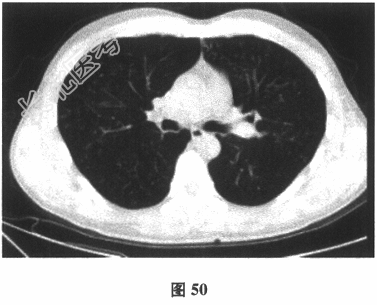

- 多项选择题3.[提示]患者行胸部CT(图50)、血气分析,提示轻度低氧血症, 冷凝集试验1:16阳性, 痰培养铜绿假单胞菌,考虑诊断为弥漫性泛细支气管炎。根据目前的诊断, 该患者最适合的治疗方案是( )